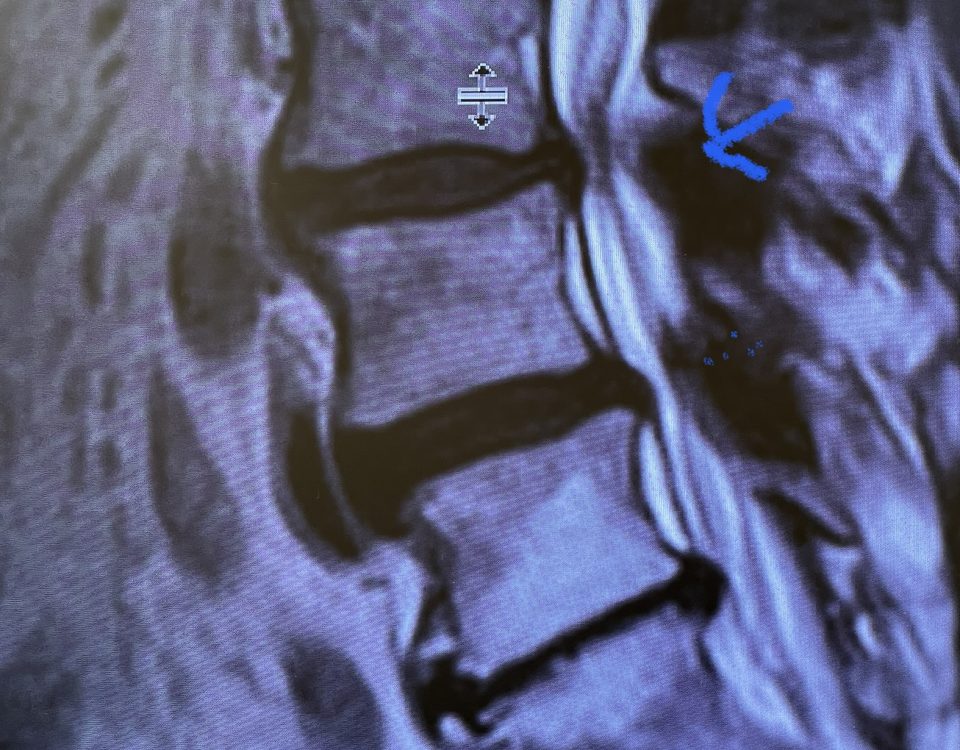

The spinal synovial cyst is one of the most interesting expressions of spinal instability. They emanate from the synovial lining of a degenerated facet joint that […]